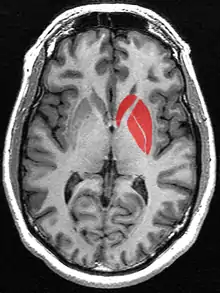

![]() البطامة، النواة المذنبة، اللوزة = أرجواني

![]() بطامة | |